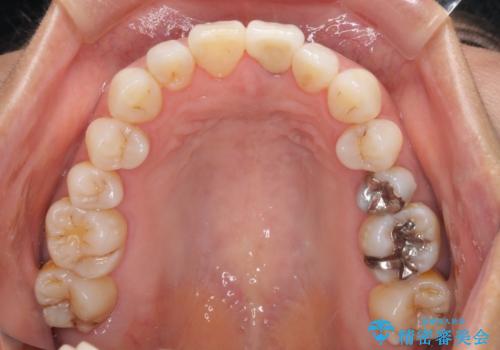

- 10年以上前に神経を取り除いた前歯の変色が気になるとのことで来院された患者様です。

レントゲン写真より、歯根の炎症が認められなかったため、ファイバーコアによる土台築製後、オールセラミッククラウンにて補綴することとしました。